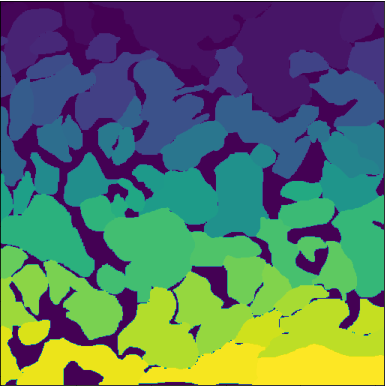

6.2 GT comparison

Samples of images generated using our pipeline were shown to an expert experimentalist for the selection of preprocessing-projection method combinations which could provide comprehensive, useful and different information about the cardiac cell networks imaged for GT annotation. Selected methods are shown in Figure 6. GT annotations generated using the selected projections were compared with annotations generated from composite grayscale images obtained using conventional frames stacking and averaging methods [7]. Due to visualisation constraints in old composite images due to low brightness and impaired image quality, only 77 images were analysed at this stage. New GT () and old GT () annotations were compared using two levels of analysis:

Pixel-Level Agreement (Semantic segmentation)

At this level, we evaluated the semantic agreement between and using several metrics: Intersection over Union (IoU), which measures the extent of overlap between the two GTs, Background Mismatch (BG ), which quantifies the percentage of pixels labelled as background in one GT but pertaining to foreground in the other. Results of these evaluations are presented in Table 3.

As illustrated in Table 3, we observed notable variance in IoU scores across the dataset. To better understand this variability, we visually examined three representative cases from and , one with the lowest IoU (Figure 6(a) and (d)), one with the highest (Figure 6(c) and (f)), and one approximating the metric’s median (Figure 6(b) and (e)). Our analysis revealed that images taken at higher microscope magnifications (Figure 6(c) and (f)) yielded higher IoU scores between and , indicating alignment between the two GTs. This suggests that increased resolution may facilitate consistent segmentation.

Metric IoU BG Mo BG Mn CA CA CC CC mean 86.08 6.86 5.15 4106 5452 47 74 p25 84.19 5.06 3.46 2354 3495 35 50 median 86.43 6.56 4.72 2820 4238 52 75 p75 88.69 8.31 6.06 4172 6174 61 91 min 75.89 1.52 1.64 1372 2503 12 11 max 92.40 15.13 14.36 21952 19286 84 171

Furthermore, in these high-magnification cases, provided clearer delineation of cellular boundaries and background regions, particularly at the image corners, where segmentation is typically more challenging. In the lowest IoU examples (Figure 6(a) & (d)), revealed more complete cell structures and extended boundaries, indicating improved visibility and segmentation accuracy.

Additionally, BG , which highlights instances where regions previously labelled as cells in were reclassified as background in , was found to be higher than BG , suggesting that noise reduction or enhanced visibility improved the accurate delineation of true cell regions in .

Cell-Level analysis (Instance segmentation)

This level focuses on instance-level comparisons. We examined metrics such as Cell Counts (CC), Cell Size (CS), and shape descriptors to assess structural differences between the GTs. The outcomes of this analysis are summarised in Table 3 and visualized in Figure 8, using Kernel Density Estimation (KDE) and box-plots.

The distribution of cell areas in exhibits a pronounced peak at smaller sizes, indicating that the new segmentation and preprocessing pipeline tends to produce a greater number of small cells, with many cell areas clustered around lower values. In contrast, the distribution for is broader, suggesting a wider range of cell sizes and less concentration around any particular value. This pattern implies that yields more consistent and generally smaller cell segmentations, whereas contains larger cells.

One of the key requirements for efficient image fusion is that the fused image must preserve all the quantitative information contained within the original video recording and contain more detailed information about the scene or object depicted than the isolated frames alone. Cell-level comparison of CA and CC in GTo and GTn annotations proved that images generated through the image fusion method presented in this study contain a higher number of cells, averaging a increase in cell count (from a median of 52 cells identified in to a median of 75 cells in ), than images generated using conventional frames stacking and averaging methods (Table 3 and Figure 2b). These results suggest two main things: 1) our pipeline is more effective than previously employed methods [7] at combining data from multiple frames while reducing temporal inconsistencies across frames caused by fluctuating fluorescence signal intensity within cells. Therefore, projected images generally retain more complete information about the cellular network for downstream annotation (Figure 8); 2) efficient noise removal and contrast enhancement by our proposed approach improves the visibility of cellular boundaries, facilitating the separation of individual cells within dense and overlapping cellular regions characterised by cellular aggregation (Figure 7). This last assumption is further corroborated by the results achieved from the analysis of pixel-level agreement between GTo and GTn. By comparing BG and BG (Table 3), is therefore evident that a higher percentage of pixels identified as cells in GTo were changed to background pixels in GTn than vice-versa. This shift suggests that noise was either removed by our projection pipeline or that improved visibility and image sharpness, especially around cellular boundaries, enabled more accurate identification of true cell regions. Therefore, as shown in Figure 7a and 7d, large cells in were often segmented into multiple smaller cells in , likely due to enhanced boundary detection. This is also suggested by the lower CA and higher cellular density recorded in than (Figure 8), where the lower amount of larger cells recorded in suggests the under-segmentation of low-brightness cellular regions with unclear boundaries from unprocessed composite grayscale images. Overall, these observations support the hypothesis that the revised preprocessing pipeline produces more precise and biologically consistent segmentations.